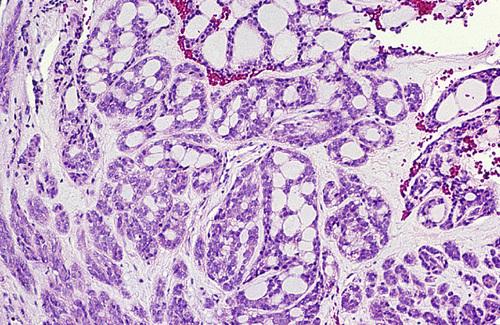

Low-power view showing a papillary cystic tumor with a lymphoid stroma. The epithelium is oncocytic, forming uniform rows of cells surrounding cystic spaces.

Warthin tumor

High-power view of epithelial lining showing double row of oncocytes with adjacent lymphoid stroma. The inner luminal layer consists of tall columnar cells with centrally placed, palisaded, and slightly hyperchromatic nuclei. Beneath this is a second layer of cuboidal or polygonal cells with more vesicular nuclei.

Warthin tumor